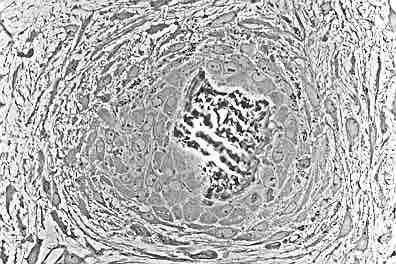

Osteoblasts

This figure shows osteoblasts creating rudimentary bone tissue.

Osteons are units or principal structures of compact bone. During the formation of bone spicules, cytoplasmic processes from osteoblasts interconnect. This becomes the canaliculi of osteons.

Since bone spicules tend to form around blood vessels, the perivascular space is greatly reduced as the bone continues to grow. When replacement with compact bone occurs, this blood vessel becomes the central canal of the osteon.